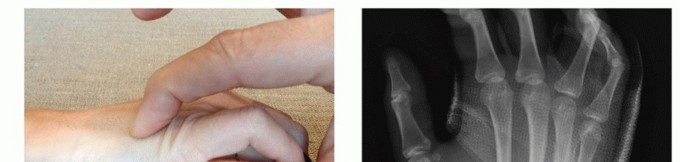

TECH FIG 4 • A-C. Patient with torsional injury to long and ring fingers leading to spiral fractures of the third and fourth metacarpals. The combined injury made it possible for malrotation to develop. D.

TECH FIG 4 • (continued) G,H. Motion at 6 weeks after surgery. The periosteum is elevated at the fracture site to assist with assessment of fracture reduction. As much of the interosseous muscle is left attached to the metacarpal as feasible to preserve blood supply to the bone.The fracture is reduced and provisionally stabilized with reduction clamps (TECH FIG 4D).

LAG SCREW FIXATION

Long oblique and spiral fractures whose lengths are at least twice the diameter of the bone at the level of the fracture are amenable to limited fixation with screws only (see TECH FIG 4A-C).Appropriately sized lag screws (1.4 to 2.7 mm) are placed. Typically, two or three screws are used (TECH FIG 4E,F).The first screw is placed perpendicular to the fracture in order to compress it and the second screw is placed perpendicular to the bone to resist longitudinal forces.In order to get proper compression with a lag screw construct, it is important to overdrill the near cortex.When using a 2.0-mm screw system, a 1.5-mm drill bit is used to drill both cortices. The near cortex is then overdrilled with a 2-mm drill bit.A countersink is used to maximize contact between the head of the screw and the bone. The size of the screw is measured and an appropriately sized screw is placed.The periosteum and interosseous muscle fascia are reapproximated to cover the screws. The juncturae tendinum are repaired and the skin is closed in standard fashion.The hand is then immobilized with the MP joints flexed 70 to 90 degrees with a forearm-based splint. Early motion can be started as early as 4 to 7 days, depending on fracture stability (TECH FIG 4G,H).